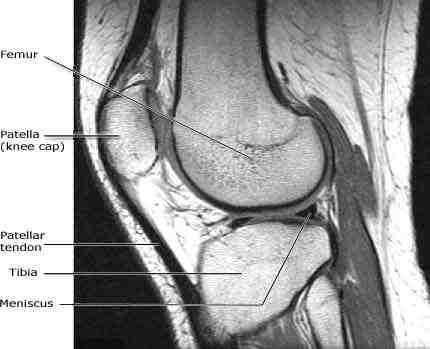

If your body has metal or electronic devices, such as artificial fittings or heart valves, a pacemaker, or rods, plates, or screws that hold the bones in place, be sure to notify the technician. See the article : Tooth Illustration. The metal can interfere with the magnetic field used to create the MRI and pose a safety hazard.

Pins, Plates, and Metal Joints MRI does not affect the replacement of metal well attached to bone, such as the hip and knee joint. The metal does not heat up or move in response to the machine. Read also : Affordable Implants. However, if the metal is located near an organ, such as the prostate, the problem may be distortion.

Risks of the procedure However, due to the use of a strong magnet, MRI cannot be performed in patients with implanted pacemakers. Intracranial aneurysm clamps. Cochlear implants.

The presence of metal can be a serious problem in magnetic resonance imaging because (1) magnetic metals can experience force in the scanner, (2) long wires (e.g., in pacemakers) can cause induced current and heating from the RF magnetic field, and (3) metals cause static (B0) magnetic field unevenness, causing serious …